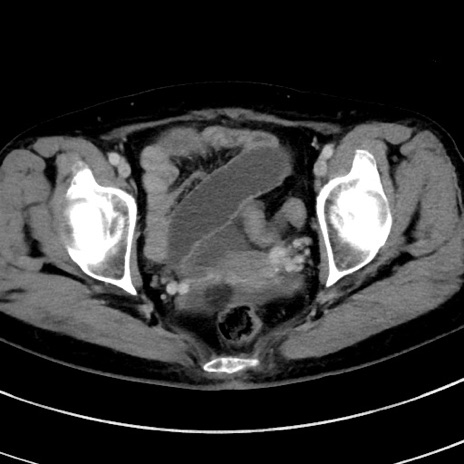

症例9(横断像)

【症例】 60歳代女性

【主訴】むかつき、みぞおちの痛み

【現病歴】3日前よりむかつきがあり、食事がとれない。

【既往歴】糖尿病

【身体所見】発熱なし、心窩部圧痛軽度あるも、腹膜刺激症状なし。

【データ】WBC 7400、CRP 1.92